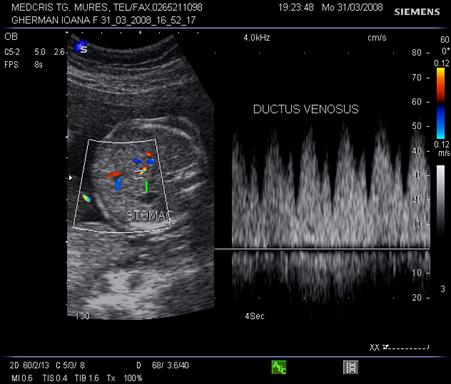

Ductul venos

In sectiune sagitala ductul venos apare ca o continuare a venei ombilicale spre vena cava inferioara. Inclinatia creste de la 7 la 48 la locul de unire cu vena cava. Aspectul este de "trompeta" de la circa 17 saptamani.[14,17]

Aspectul eco Doppler normal in ductul venos este de sistola ventriculara, diastola ventriculara, contractie atriala, deci aspect trifazic.

Ductul venos creaza o comunicare intre sistemul venos periferic ombilical si sistemul venos central al fatului. Gradientul presional in ductul venos se modifica in caz de suferinta fetala.

Daca are loc centralizarea circulatiei, prin scaderea presiunii venoase centrale, scade presiunea in ductul venos in timpul contractiei atriale, cu aparitia reverse - flow.( unda a negativa ) [19]

Fig. nr.329. Ductus venosus( sageata ) la o sarcina de 16 sapt,. sectiunea sagitala fetala

Fig. nr. 330. Ductus venosus la doppler pulsat cu CFM , la o sarcina de 27 sapt. Se remarca aspectul normal trifazic al undei .

Fig. nr. 331. Ductus venosus la doppler pulsat si CFM , la 21 sapt, fat in sectiunea transversala a stomacului